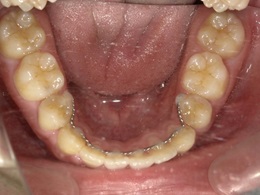

治療前下顎

治療後下顎